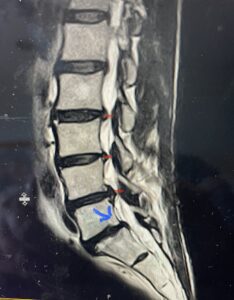

Fig. 2) T2-weighted lumbar MRI demonstrating severe lumbar stenosis (red markers) and a grade 1 spondylolisthesis at L5-S1 (blue arrow)

This 59 year-old female had severe bilateral leg pain and numbness over a 6-month period. The patient had failed conservative treatment with physical therapy, chiropractic care, and medications. MRI revealed that she had severe lumbar stenosis with a grade 1 spondylolisthesis or “slipped disc” at L5-S1 (Fig. 2). In addition, she had previously undergone both front and back surgery for severe cervical stenosis where her posterior hardware had failed because of her severe osteoporosis requiring us to remove the posterior hardware. This required her to have an anterior or front operation which allowed better fixation to her spine because of the load-sharing nature of the interbody grafts in addition to her anterior cervical plate (Fig. 3).